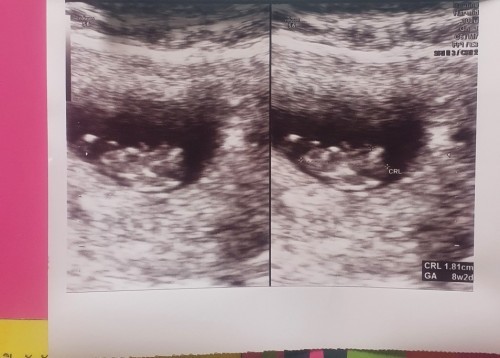

8wkeเต้นอยู่ที่168/นาที❤️❤️

ของเราเจอตอน8วีค2วันคะ